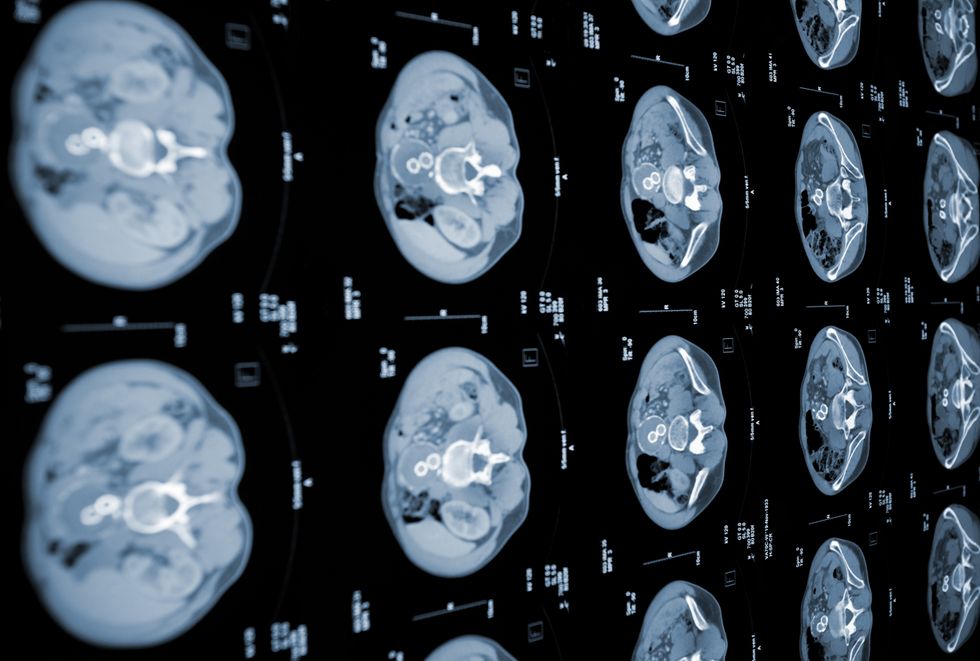

Scientists have uncovered a crucial connection between cellular stress, inflammation and the development of the deadliest forms of cancer known as pancreatic ductal adenocarcinoma (PDAC).

The pancreatic cancer, by far the most common form of the disease, makes up around 90 per cent of pancreatic malignancies.

Now, new findings suggest that precancerous cells must adapt to inflammatory conditions and stress to transform into malignant tumours, which could enable detection of PDAC before it reaches life-threatening stages.

The findings hold promise for precision medicine applications, particularly in developing early screening methods to identify precancerous cells.